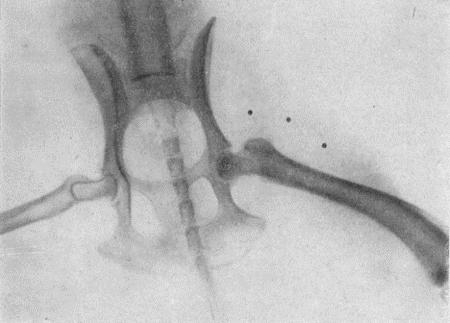

Так как клинические признаки не всегда ясно выражены, то для уточнения диагноза и определения местоположения инородного тела прибегают к рентгеноскопии или рентгенографии (см. рис. 55, 56, 57, 58, 59).

Вспомогательным диагностическим методом может служить фистулография, для чего в свищ вводят 40 % раствор сергозина, а затем производят рентгенографию.